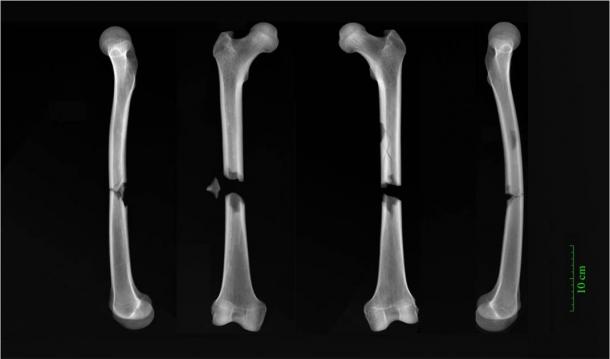

Dr. Jenna Dittmar from the After the Plague Project at the University of Cambridge’s Department of Archaeology was lead author of the new study. The professor wrote that by comparing the skeletal trauma of remains buried in various locations within a city like Cambridge, “we can gauge the hazards of daily life experienced by different spheres of medieval society”. The researcher noted several stand-out cases that the team found during the research including: the remains of a church friar resembling “a modern hit-and-run victim, and bones that hint at lives blighted by violence.” The friar had complete fractures halfway up both his femurs and it was concluded that whatever caused both bones to break in this way “must have been traumatic, and was possibly the cause of death,” said Dittmar.

X-rays of butterfly fractures to both femora of an adult male buried in the Augustinian friary in medieval Cambridge. (Dr. Jenna Dittmar / University of Cambridge)